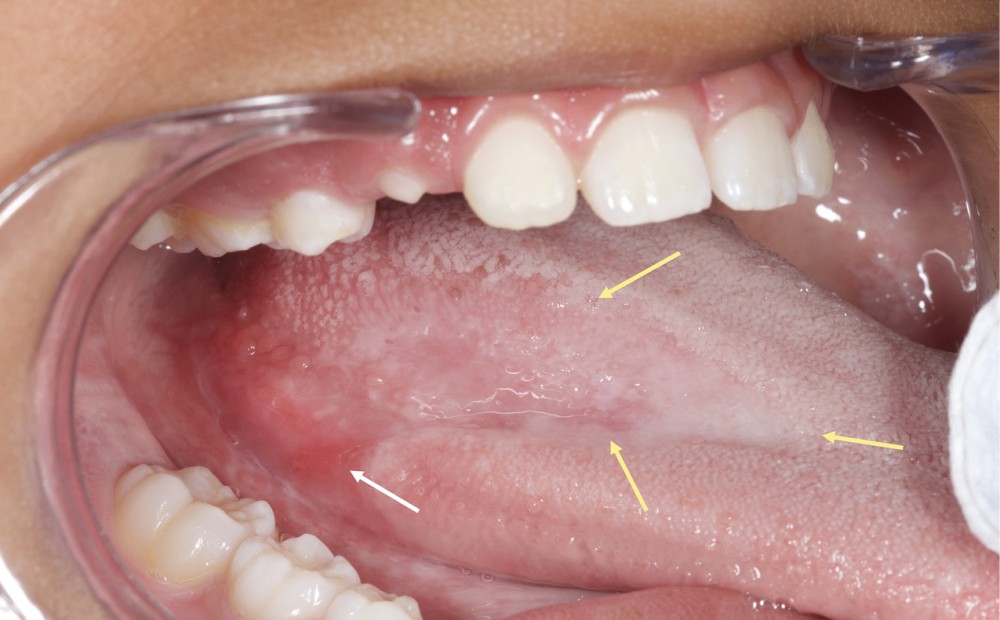

D’emblée, l’examen endobuccal met en évidence la présence d’une lésion linguale sur la face dorsale postérieure droite de la langue, bien délimitée, légèrement érythémateuse, d’aspect vernissé et atrophique avec altération ou perte des papilles. Cette plage s’étend sur 8 cm environ et rejoint une zone érosive, de plusieurs millimètres, située sur le bord de la langue. En outre, l’examen clinique révèle la présence de lésions blanches, d’aspect réticulé, au niveau de la face interne postérieure des joues, des vestibules postérieurs et du vermillon labial inférieur droit. Du côté droit, les lésions jugale, du vestibule et linguale se prolongent en continuité. Les autres muqueuses orales apparaissent saines. Par ailleurs, la palpation des muqueuses atteintes est indolore et permet d’écarter la présence d’une induration. De même, la palpation des zones ganglionnaires cervico-faciales exclut une adénopathie. Enfin, aucune atteinte cutanée n’est notée au niveau des membres et du tronc, au niveau unguéal ou du cuir chevelu.